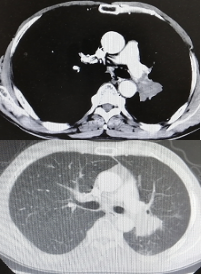

影像学-增强CT检查:左肺见不规则软组织影,包绕肺门结构,病变轴位长径约7.5cm,左肺散在结节影,最大约4.5cm;纵隔、肺门见多发淋巴结肿大,纵隔7组短径约2.0cm。

CT检查——基线

影像学-增强CT检查:治疗2周期后,左肺病灶明显缩小达52.9%,疗效评估为PR。

CT检查——治疗2周期后

治疗6周期后,左肺病灶明显缩小达58.6%,疗效评估为PR。

CT检查——治疗6周期后